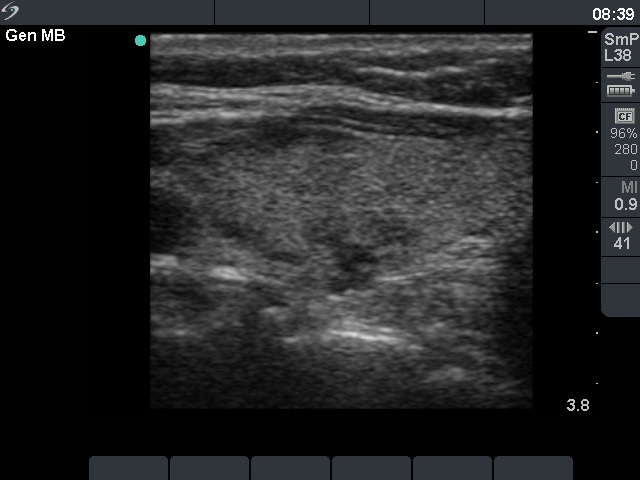

Three years after surgery (fourth row of images)

Clinical data: The patient has lost 2 kg-s in weight and has noticed an increased heart rate and nervousness for several months.

Results of blood test: TSH 0.001 mIU/L, FT4 31.9 pM/L, TSAb 9.1 U/L (normal value below 1.5).

Ultrasonography: The pattern remained unchanged.